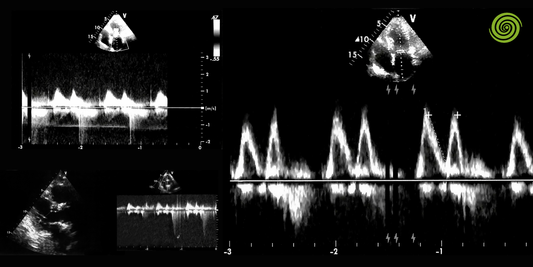

Ecocardiografía en Veterinaria: Monitoreo Preci...

La ecocardiografía es una herramienta esencial en la evaluación del corazón de los animales, permitiendo observar en tiempo real su estructura y funcionamiento sin procedimientos invasivos. La imagen obtenida con...